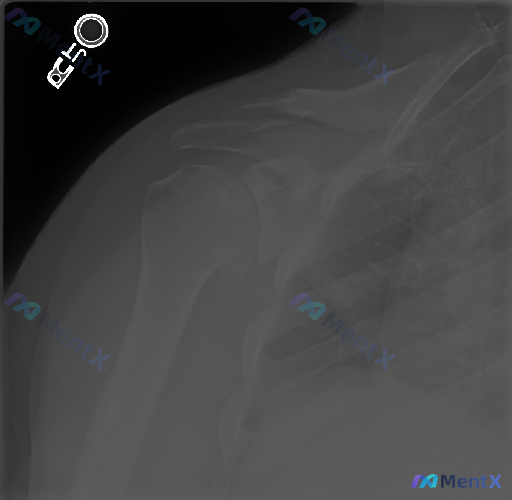

整理到一张肩关节Y形斜位(Scapular Y-view)的影像资料,原始预设提了一句“存在异常”。

- 投照标准,肩胛骨的“Y”字结构(肩胛冈、肩胛体、喙突/肩峰)显示良好

- 肱骨头基本在肩胛盂中心,前后脱位征象不明显

- 骨皮质连续,没看到明确的骨折线、骨质破坏或明显骨赘

- 肩峰下间隙、盂肱关节间隙看起来也还行,大结节附近没看到明确钙化

- 怎么看待“预设说有异常,但平片没看到明确骨性问题”这种情况?